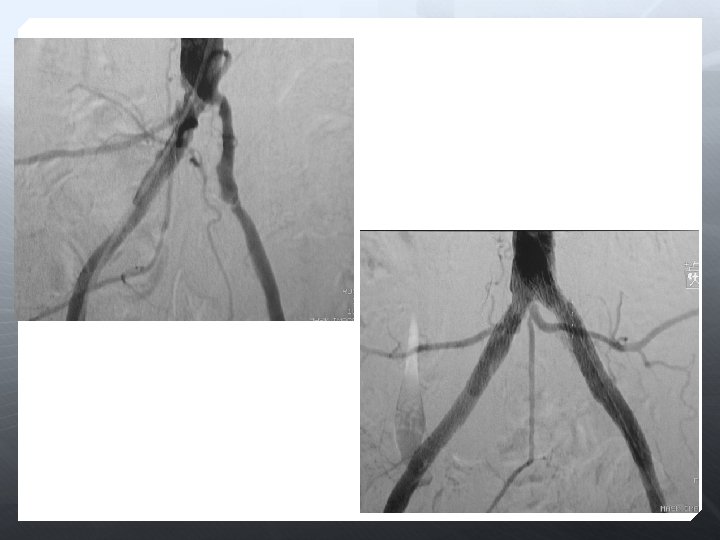

Anlamlı arteryal darlık >%50 Anlamlı basınç farkı >%10 Yakınma Klaudikasyon Kiritik bacak iskemisi Vasküler orijinli impotans

Darlık Oklüzyon Aorto-iliak Femoral-popliteal Infrapopliteal

DİZALTI

Amaç uzun dönem açıklık değil, akımı restore etmek Olabildiğince çok damar restrore edilmeli Total ayak perfüzyonu iyileştirilir 3 damar run-off ile daha iyi SFA açıklığı sağlanır Oklüzyona karşı daha dirençli